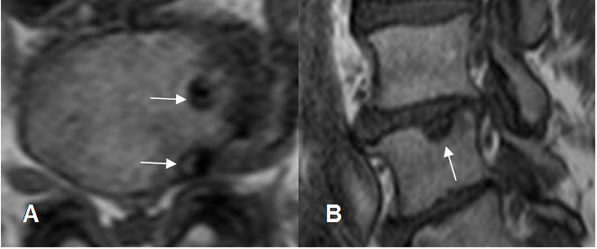

Fig 115. Nódulo de smorl.

A: RM axial en T1y B: RM sagital en T1. Defectos de bordes escleróticos en las placas terminales, por nódulos de smorl.

En las diferentes modalidades se aprecia como una indentación en la placa terminal, de bordes escleróticos, asociados o no a espondilosis y otros cambios degenerativos vertebrales. (27). (Fig 114 y 115).